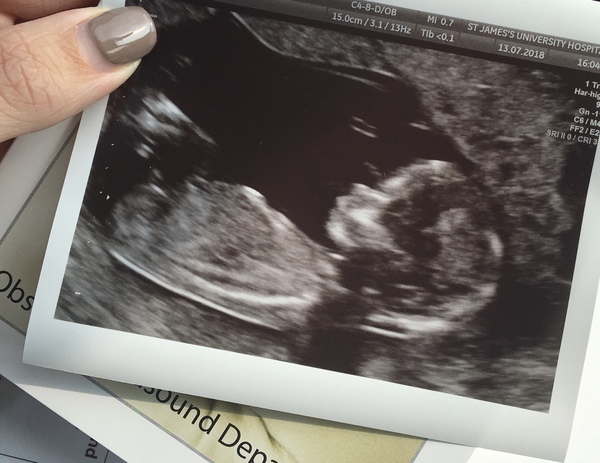

Can anyone see a nub on mine?Grin find out in 2 weeks so can confirm then!

Skull theory